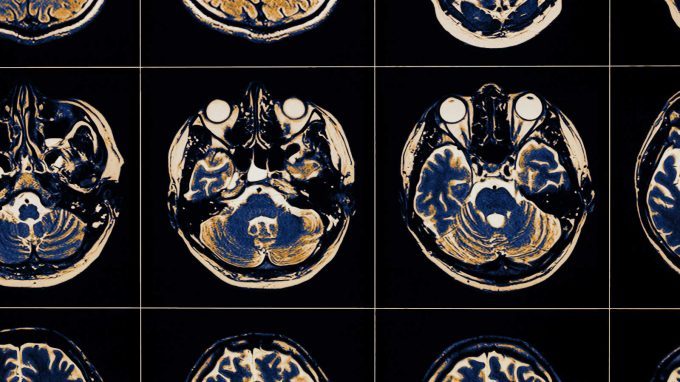

L’inibizione del sistema immunitario, dopo un danno cerebrale, porta ad un miglior recupero dal trauma cerebrale

Una ricerca sui topi è arrivata alla conclusione che agire sull'infiammazione porta a buoni risultati terapeutici nel trattamento del trauma cerebrale

I traumi cranici possono causare danni biologici al cervello irreversibili, portando il soggetto ad avere complicanze in ambito cognitivo, comportamentale o emotivo. La principale difesa immunitaria del cervello è data dalle cellule microgliali. Quali influenze possono avere queste cellule sul recupero dopo un danno cerebrale?

Dopo un trauma cerebrale si verifica un’attivazione del sistema immunitario, che si manifesta tramite un’infiammazione della zona danneggiata, agendo cosi come fattore protettivo per il cervello. Tuttavia, se l’infiammazione si protrae per troppo tempo può portare alla degenerazione neurologica con conseguente declino cognitivo (Henry et al., 2019).

I traumi cranici possono causare danni biologici al cervello irreversibili, portando il soggetto ad avere complicanze in ambito cognitivo, comportamentale o emotivo; la prognosi dipende dall’entità del danno e colloca lungo un continuum che va dal recupero completo al decesso nei casi più gravi. Il trauma cranico rappresenta una delle principali cause di morte (Alves& Bullock, 2001).

La principale difesa immunitaria del cervello è data dalle cellule microgliali: queste sono un tipo di cellule della glia che vanno a costituire la principale difesa immunitaria del nostro sistema nervoso centrale.